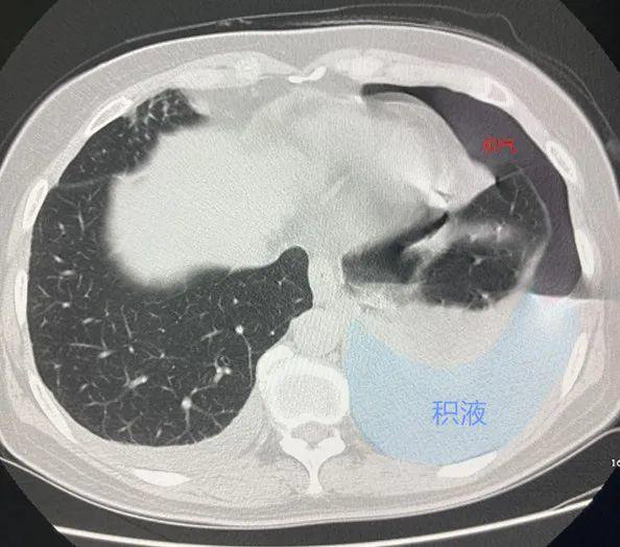

Lần này đến bệnh viện, cô được chụp CT, các bác sĩ phát hiện lồng ngực của cô có nhiều khí và chất lỏng, phổi nặng như phổi bò, có thể là bệnh lao nên cần điều trị ngay! Nghe tin này, cô Hồ và gia đình vô cùng lo lắng nên đã lên bệnh viện tuyến trên để khám xét kĩ lưỡng hơn tại Khoa Phẫu thuật lồng ngực của Bệnh viện Chữ thập đỏ Hàng Châu.

Cô Hồ bị tràn dịch màng phổi lớn.

Sau khi nhập viện, cô Hồ được tiến hành nội soi lồng ngực trái và dẫn lưu, trong quá trình dẫn lưu, một lượng lớn dịch mủ chảy ra từ ống ngực.